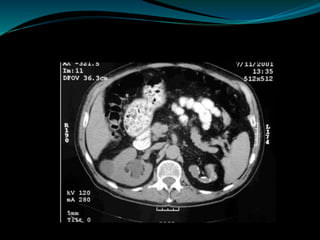

Computed Tomography

 The most common findings on contrast-enhanced CT

include renal parenchymal masses and scarring, thick

urinary tract walls (ureter and bladder) and extraurinary

tubercular manifestations particularly in miliary TB .

 CT allows for evaluation of renal function, grading of

hydronephrosis and parenchymal scarring .

 CT is most sensitive in detecting renal calcifications .